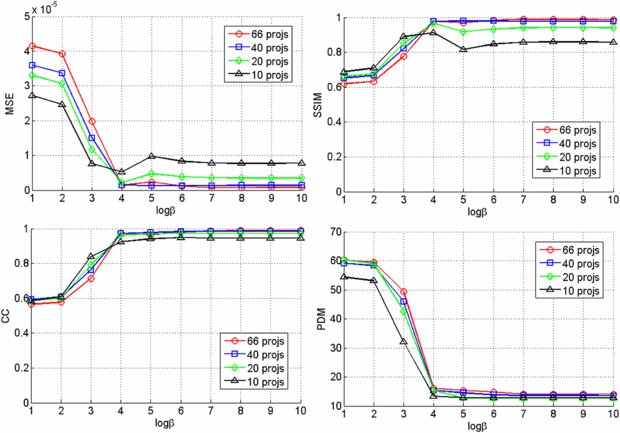

Since we used six beads for registering the CBCT prior volume to the post-injection x-ray projections and there is no soft tissue in the phantom, the registration was very accurate and the difference images clearly show the region of change while other structures are eliminated as shown in figure 3. The VOCs reconstructed from 15, 30, 45, 60 difference images by the PL reconstruction method with different β values (101–1010) were compared to the CBCT ground truth, and figure 4 shows the similarity measure plots as a function of β. It is observed that the reconstruction is noisier at lower β where the estimate is closer to ML estimate, but becomes smoother at higher β where the reconstruction is more regularized by the penalty. Since the shape and structure of the bone cement was not so complicated and the registration was accurate, the overall reconstruction quality was not degraded even when we reduced the number of images and the similarity plots show similar reconstruction performance regardless of the number of images. It is also observed from these plots that the overall reconstruction quality is lower at lower β because it is noisier, but is similarly good when β becomes large. Figure 5 shows an example of slice images of the VOC reconstruction computed from 15 projections after 100 iterations with β = 107 (chosen from figure 4) and its fusion with the prior volume. The reconstructed VOC with prior volume showed significantly reduced artefact compared to the FBP reconstruction (Feldkamp et al 1984) computed from the same 15 post-injection x-ray images.

Standard imageFigure 4. Similarity measures for different number of projections and β values.

Figure 7 shows example images of the pre- and post-injection x-ray projections and the computed difference images. Since there was only negligible motion of the cadaver and the C-arm between these two scans, the difference image clearly shows the bone cement while other structures are eliminated. Note that this subtraction process is commonly used in digital subtraction angiography (Heautot et al 1998, Bidaut et al 1998, Anxionnat et al 2001). Similarity measures between the reconstructed VOCs and the ground truth for different β values are plotted in figure 8. Although there was noticeable reconstruction quality degradation when only 10 images were used, it was minor when 20, 40 and 66 images were used. Figure 9 shows example slice images of the VOC reconstruction computed from 20 projections and merged with the prior volume for β = 104 that was chosen based on the similarity measures shown in figure 8. Unlike the FBP reconstruction computed from the same 20 projections, both the surgical change including extravasation and the unchanged patient anatomy are clearly visible in the VOC reconstruction.

Standard imageFigure 8. Similarity measures for different number of projections and β values.